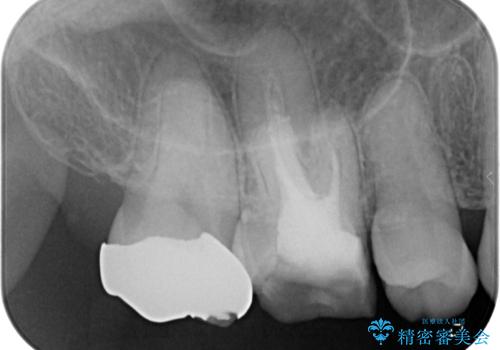

- 奥歯の金属の詰め物が取れたとのことで来院された患者様です。中学生の頃に根管治療を行い、そのあと金属の詰め物をいれていたそうです。

中学生のころに根管治療をしてから特に症状がなく、レントゲンでも病変を認めないため患者様と相談し、再度根管治療は行っていません。